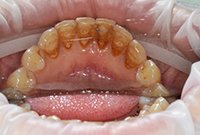

Изменения тканей, которые окружают корни зубов, к сожалению, неизбежны и с возрастом наблюдаются у всех, однако в разном объеме. Так, на развитие пародонтита влияет болезнетворная микрофлора полости рта, которая есть у каждого из нас, но на мы в силах повлиять на ее количество.

Сохранить зубы и пародонт помогает правильная гигиена полости рта дома и в кресле стоматолога, а также своевременное протезирование и имплантация, которые замещают удаленные зубы и равномерно распределяют жевательную нагрузку, не позволяя костной ткани атрофироваться.

Таким образом, по мнению стоматологов, риск возникновения болезней десен на 80% зависит от сознательности самого пациента.